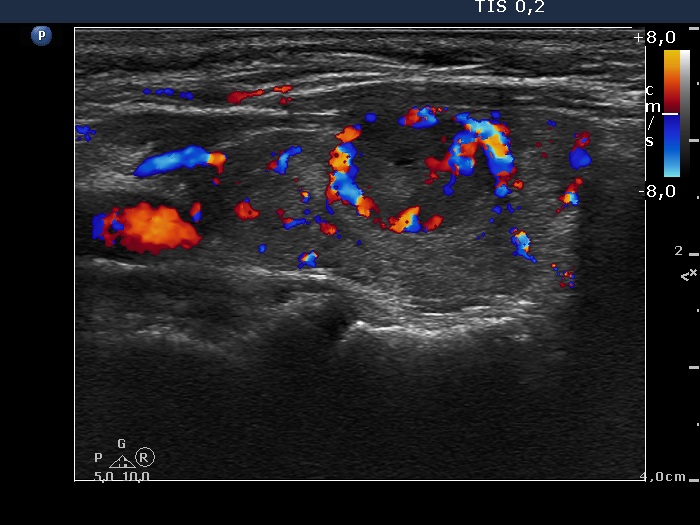

Discrete lesion or nodule in Hashimoto's thyroiditis - case 17 (782) (ultrasonographic picture 6)

Right lobe, longitudinal view, color Doppler mode. The lesion has both perinodular and intranodular blood flow.